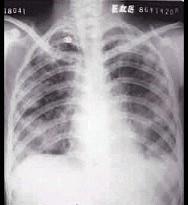

问题 男性,45岁,有糖尿病史,突起寒战、高热,咳嗽,快脓性痰,伴胸痛2天,X线显示双肺实变,其中可见多个液气囊腔(如图),最可能的诊断是 ( )

选项 A.葡萄球菌肺炎 B.肺炎支原体肺炎 C.肺炎链球菌肺炎 D.肺炎衣原体肺炎 E.病毒性肺炎

答案 A